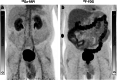

Purpose: FAPI ligands (fibroblast activation protein inhibitor), a novel class of radiotracers for PET/CT imaging, demonstrated in previous studies rapid and high tumor uptake. The purpose of this study is the head-to-head intra-individual comparison of 68Ga-FAPI versus standard-of-care 18F-FDG in PET/CT in organ biodistribution and tumor uptake in patients with various cancers.

Results: A total of 71 patients were studied of, which 28 were female and 43 male (median age 60). In 41 of 71 patients, the primary tumor was present. Forty-three of 71 patients exhibited 162 metastatic lesions. 68Ga-FAPI uptake in primary tumors and metastases was comparable to 18F-FDG in most cases. The SUVmax was significantly lower for 68Ga-FAPI than 18F-FDG in background tissues such as the brain, oral mucosa, myocardium, blood pool, liver, pancreas, and colon. Thus, 68Ga-FAPI TBRs were significantly higher than 18F-FDG TBRs in some sites, including liver and bone metastases.

Conclusion: Quantitative tumor uptake is comparable between 68Ga-FAPI and 18F-FDG, but lower background uptake in most normal organs results in equal or higher TBRs for 68Ga-FAPI. Thus, 68Ga-FAPI PET/CT may yield improved diagnostic information in various cancers and especially in tumor locations with high physiological 18F-FDG uptake.